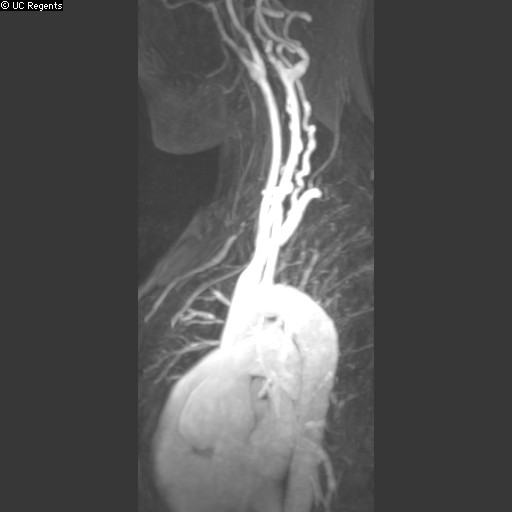

In women, Dr. Ordovas says, it's usually their distal smaller vessels that are abnormal, known as coronary microvascular disease or small vessel heart disease. As a radiologist, what you really want to look at is the appearance of the heart muscle to decide if it is not receiving enough oxygen, which is called ischemia. You don't only look at the "tubes", but you look at the following aspects of the cardiac muscle for malfunction or amount of scarring.

Cardiac MRI provides a unique way of imaging the "target" and not the "tube" that brings blood to it. Such images can help with better overall diagnosis which can help reduce heart disease mortality rates in women.